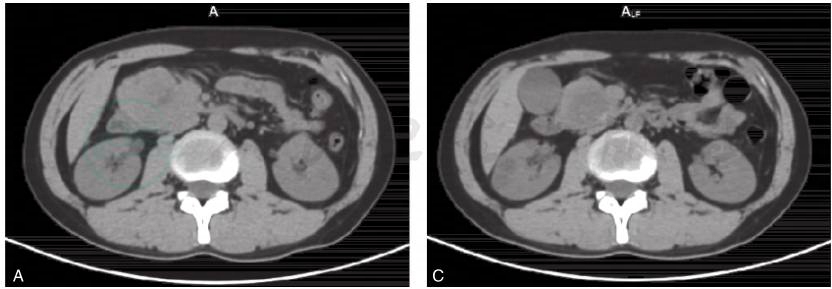

图1 68Ga-DOTA-NOC PET/CT评价(肽受体放射性核素治疗PRRT疗效)

患者,男,25岁。胰腺神经内分泌肿瘤。经过4次PRRT后,肿瘤原发病灶缩小50%,症状基本消失,肿块中央有部分坏死。分别为治疗前CT图(A)、治疗前PET/CT融合图(B)、4次PRRT治疗后CT图(C)和4次PRRT治疗后PET/CT融合图(D)。